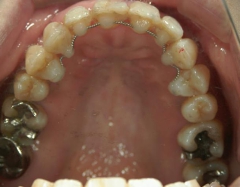

矯正歯科(全顎ワイヤー矯正)治療後

矯正歯科 治療後